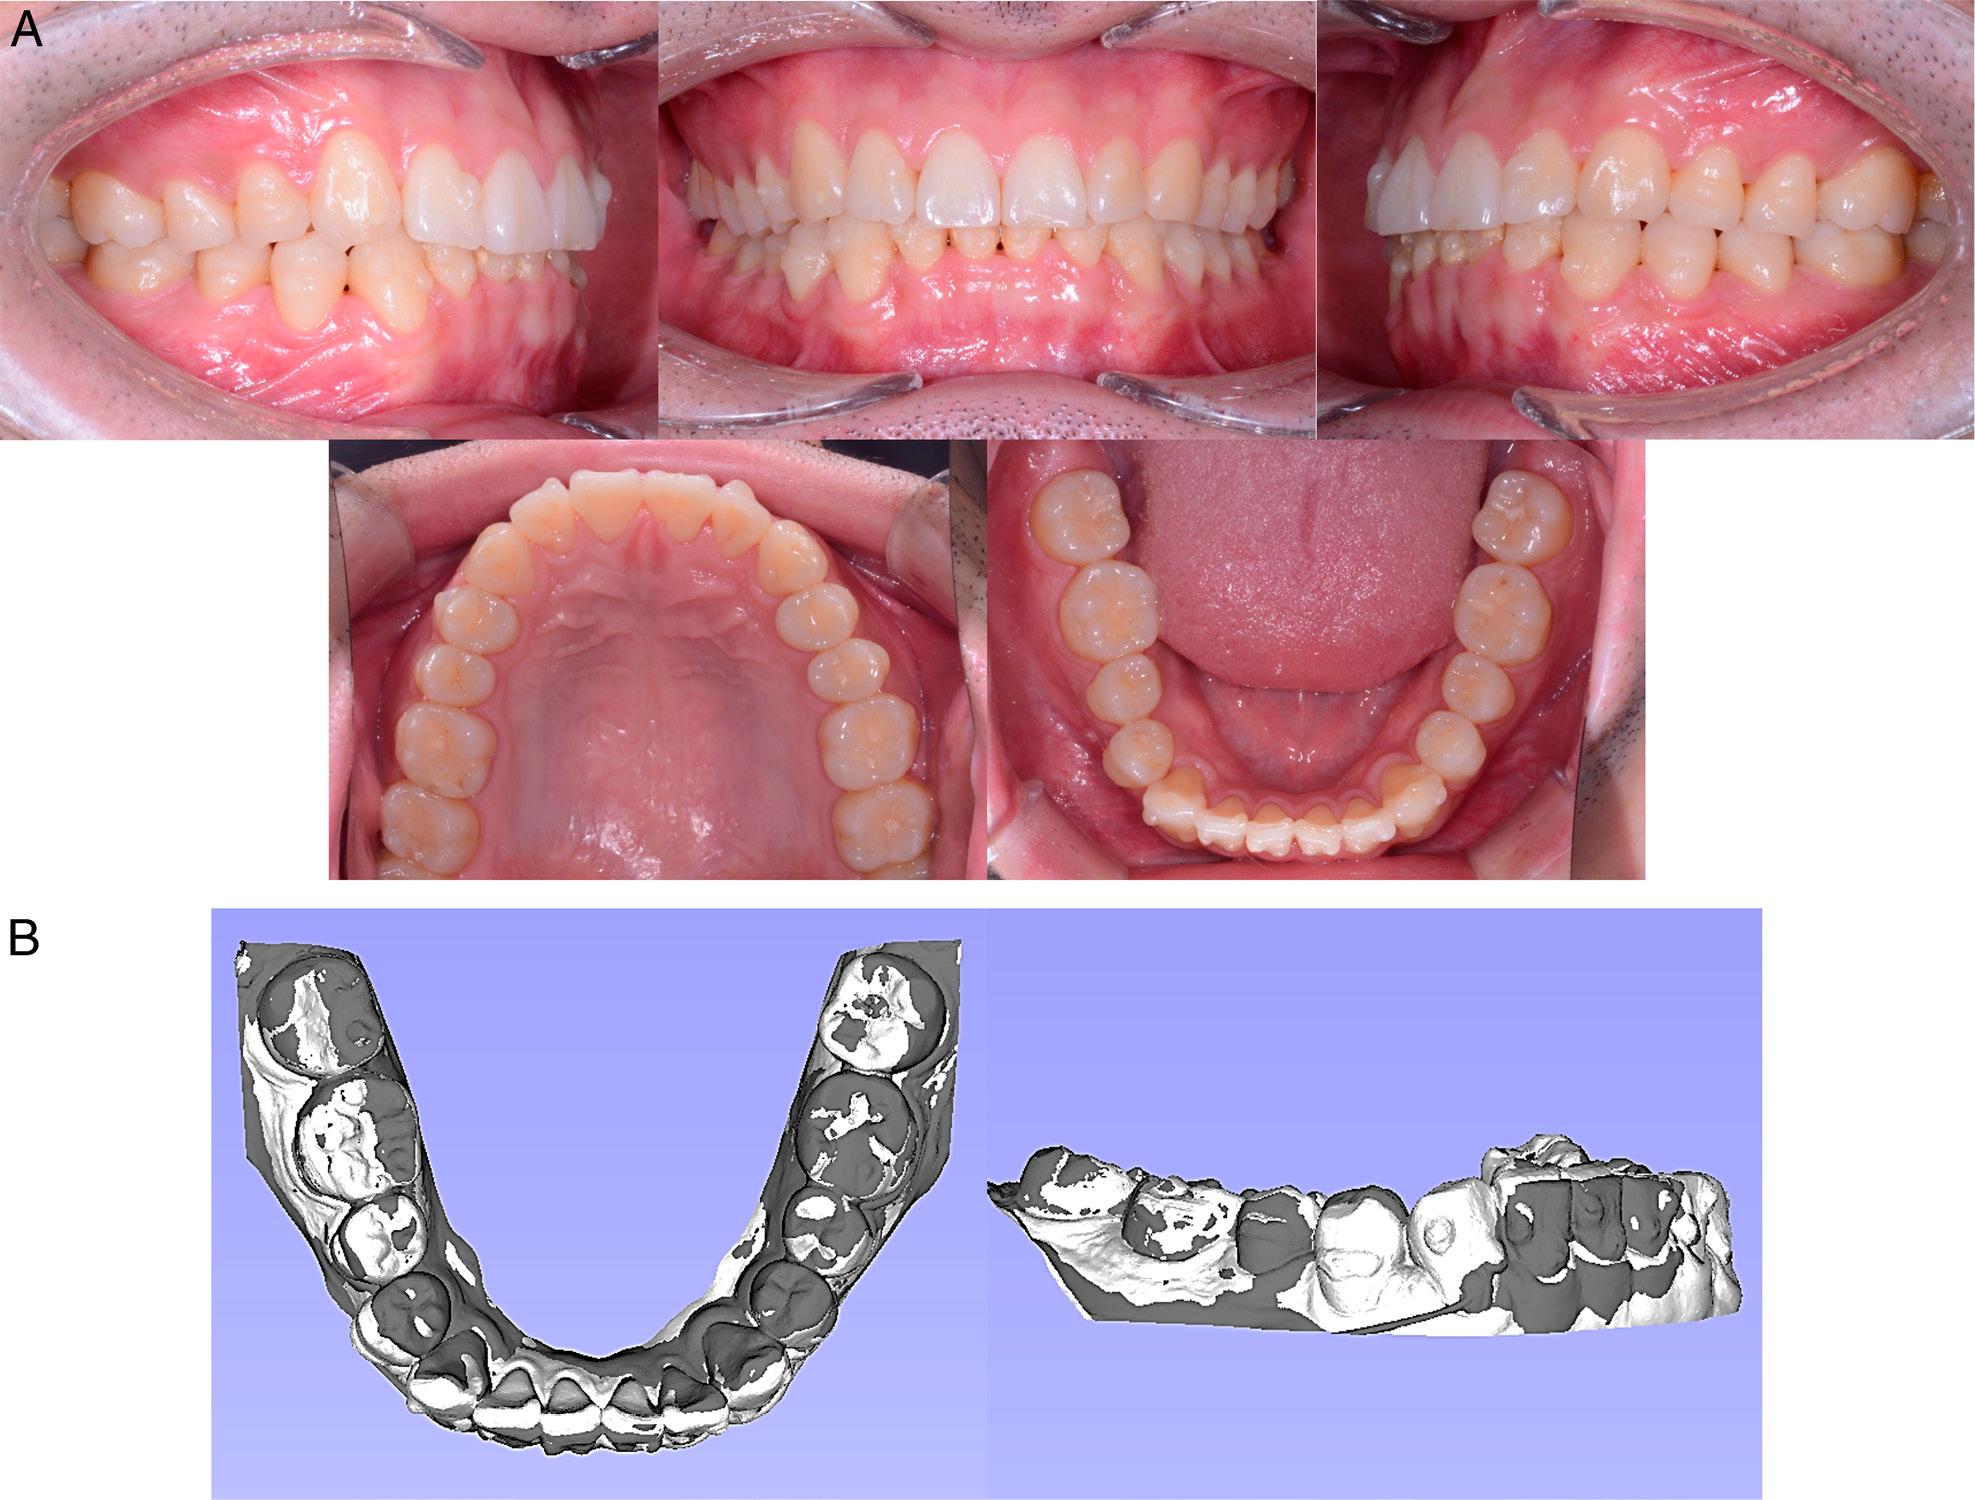

After 12.5 months of treatment, the first course of clear aligners was completed (Figure 5). The mandibular anterior crowding was alleviated, and the mandibular arch form had been modified into an ovoid shape. IPR reduced the mandibular anterior teeth size by 1.3 mm, with a resultant Bolton anterior and overall ratio of 76.2% and 91.8%, respectively. At this stage, the rotation and angulation of the right mandibular canine still required improvement.

Treatment progress at 12.5 months. A. Intraoral photographs. B. Model superimposition. The white colour denotes the model at eight months, and the dark colour represents the 12.5 month stage. The registrations were performed on the occlusal surfaces of the first and second molars.